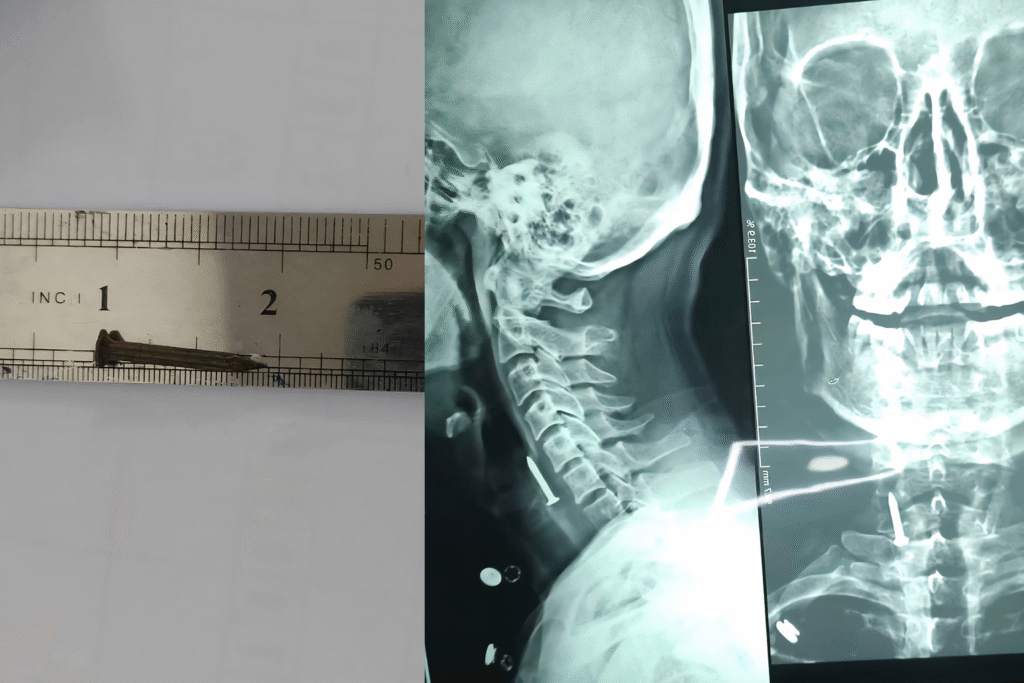

هاووڵاتییەکی تەمەن 36 ساڵ بزمارێک قوت دەدات و لە نەخۆشخانە بۆی دەردەهێنن.

ئەمڕۆ یەکشەممە 2ی تشرینی یەکەمی 2025 بەڕێوەبەرایەتی گشتی تەندروستی سلێمانی ڕایگەیاند؛ لەلایەن تیمی ئێشکگری نەخۆشخانەی كۆئەندامی هەرس و جگەری فێرکاری، بزمارێک لە گەروی چارەخوازێکدا دەرهێنرا.

بەڕێوەبەرایەتی گشتی تەندروستی نەخۆشخانەکە لەگەڵ بڵاوکردنەوەی چەند وێنەیەکی نەخۆش و بزمارەکە، ئاماژە بە تەمەنی چارەخوازەکە دەدات و دەڵێت، تەمەنی 36 ساڵە.